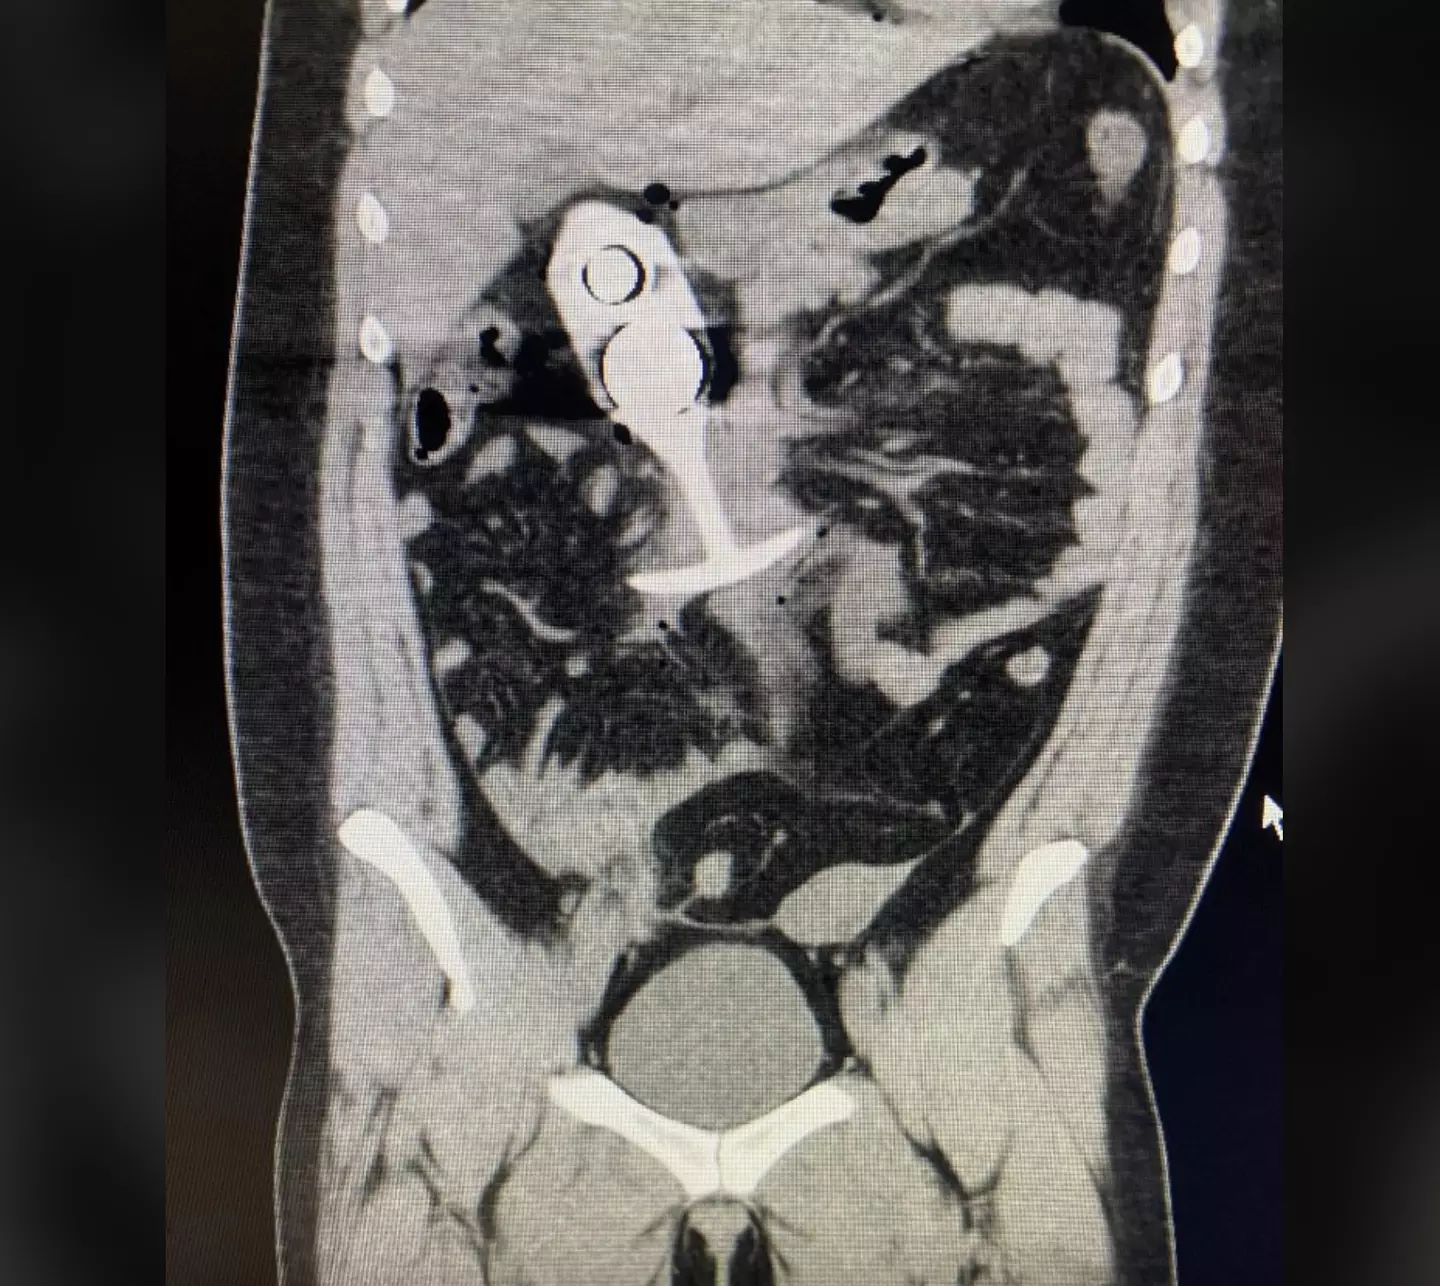

An image of the toy has been circulating online, much to the horror of social media users.

The picture of the alleged incident was shared by X (formerly Twitter) user ‘DreadPirateZero’, who wrote: ” “Never wear a butt plug to your MRI appointment. My god….”